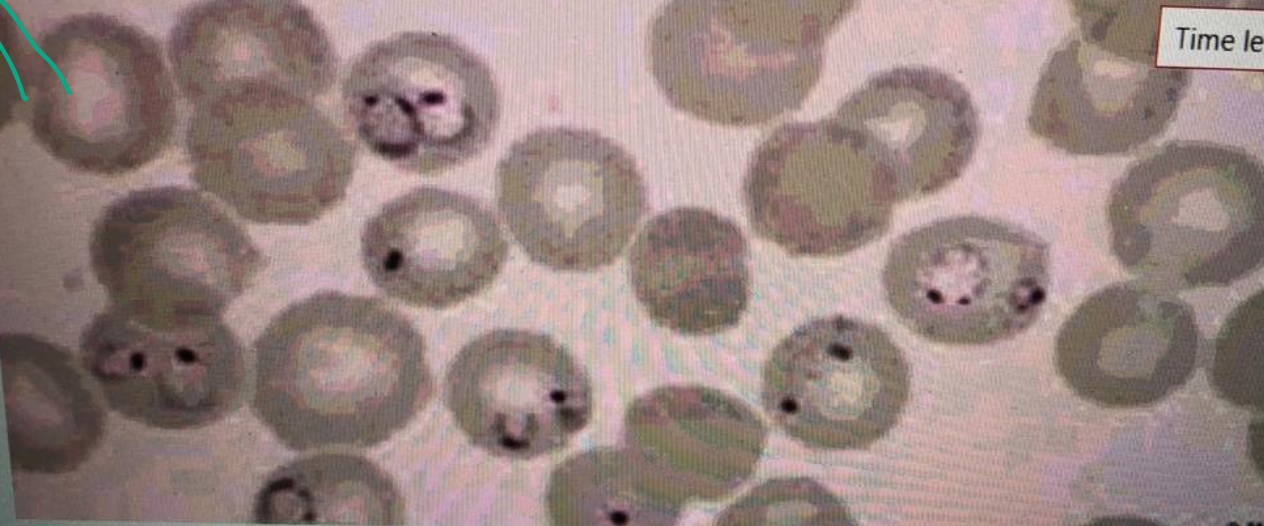

A 20-year-old male comes with fever since 5 days. Fever is episodic. The peripheral blood film is shown below.

A 20-year-old male comes with fever since 5 days. Fever is episodic. The peripheral blood film is shown below.

- What is your diagnosis based on the abnormality on the slide?

- Malaria.

- Outline 2 causes of anemia in this infection?

- Mechanical destruction of RBCs, reduced erythropoiesis in the bone marrow.

- Outline any 3 features of severe form of this infection? Z

- Cerebral malaria, blackwater fever, hypoglycemia

- Name any 2 medicines used to treat this infection, and one of them used during pregnancy?

- Hydroxychloroquine (Pregnancy), mefloquine.